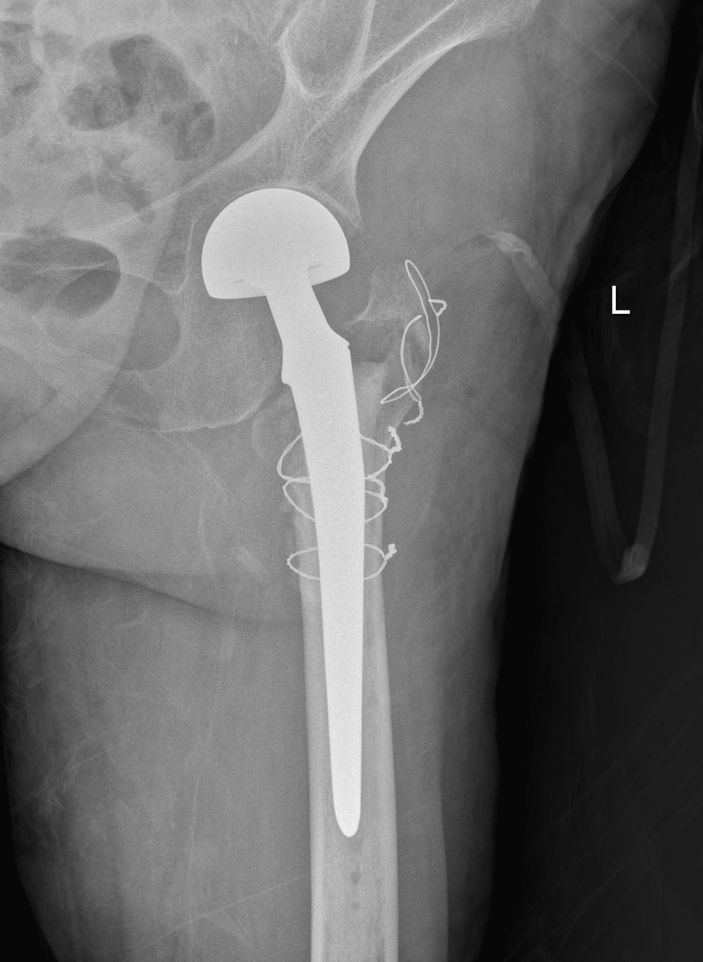

40月20日,林老太各項生命體征平穩,可耐受手術。在充分的術前準備後,外四科主任吳志斌帶領團隊爲林老太實施手術治療。吳主任充分考慮老人家的骨折特點,采用人工股骨頭置換術,術中給予安裝雙動人工股骨頭,複位髋關節,并仔細把控每一個細節,确保髋部良好的活動性和穩定性,以及雙下肢等長,手術十分成功。

△術後